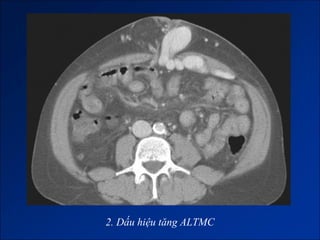

2. Dấu hiệu tăng ALTMC